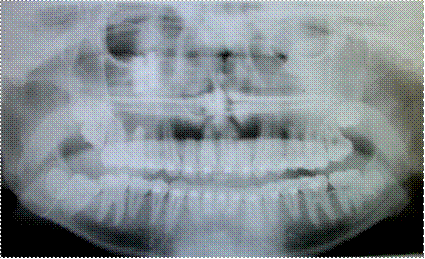

Нарушение функции жевания отмечено (со слов родителей) у всех обследованных пациентов. Наличие вертикальной щели между передними зубами (в среднем 6 мм.) приводит к затрудненному откусыванию пищи и дополнительной функциональной нагрузки на боковые зубы (рис. 3.2.3).

Рис. 3.2.3. Изображение несмыкания резцов. Наличие вертикальной щели между резцами (в среднем 6 мм.).